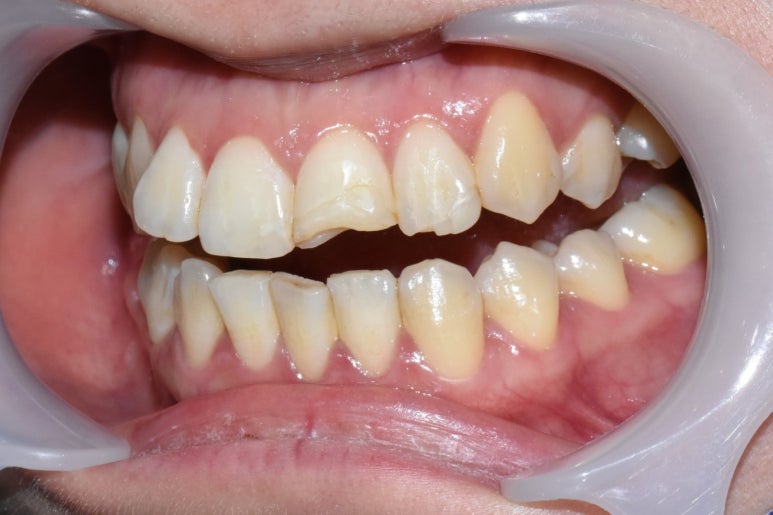

Case 1.

깨진 앞니 레진치료 전후

치아 2개가 깨져있는 상태였는데 환자분이 적게 깨진 치아말고 더 많이 깨진 치아만 치료를 원하셔서

레진으로 진행했습니다.